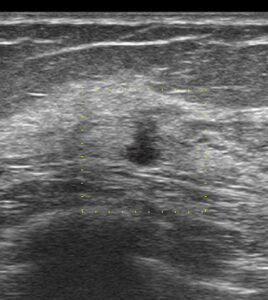

初回の検診エコー(今回送られてきたもの)

縦長! 不整型!

これ(去年に何もなかったのに、しかも60歳代)で要精査に何故しない!!

別角度

やっぱり、どう見ても「癌疑い」

何で、カテゴリー2で要精査としなかったのだろう。